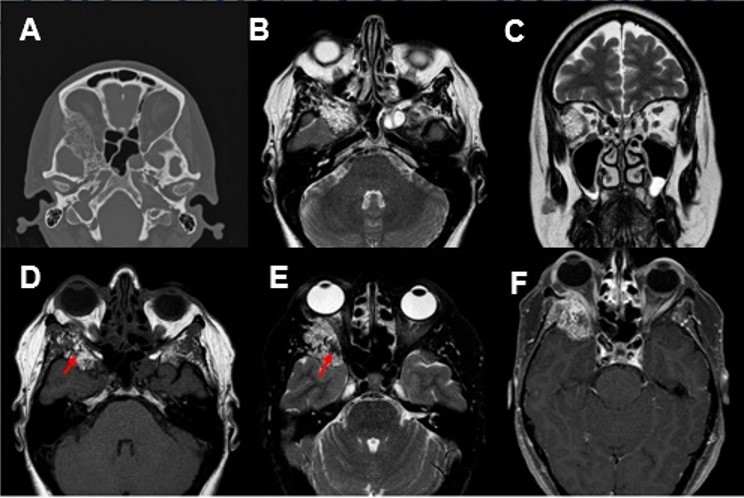

A. TC, axial: Lesión osteolítica de aspecto multiseptado que remodela las alas del esfenoides y pared lateral de la órbita derecha sin signos de agresividad (de márgenes lobulados y bien delimitada, no reacción perióstica ni disrupción cortical).

Respecto al diagnóstico por imagen, en la TC se presenta como una lesión lítica, bien definida y con borde escleroso en 1/3 de los casos. Puede improntar sobre la cortical, sin destrucción de la misma. Es característico el engrosamiento trabecular, con patrón en “en panal” o “rueda de carro”. Característicamente la trabeculación es vertical con tejido blando/grasa interpuesta. En la RM son tipicamente hiperintensos en secuencias T1 si el componente graso es mayoritario; si hay mayor componente de engrosamiento trabecular predominio hipointenso. Son heterogéneamente hiperintensos en secuencias T2 y realza de forma intensa y heterogénea con contraste paramagnético.